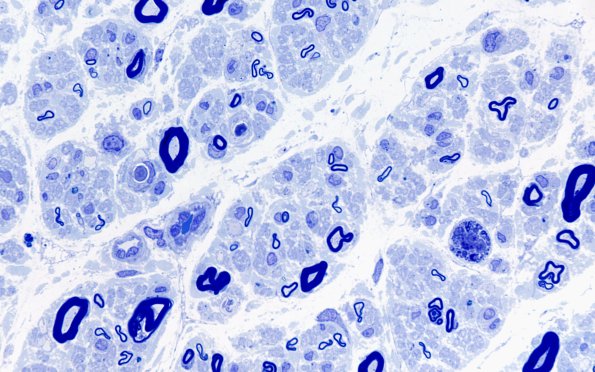

Washington University Experience | PERIPHERAL NEUROPATHY | 13 POEMS SYNDROME | 1A2 POEMS (Case 1) Plastic 100X 9

The most striking feature was loss of large and small (L>S) myelinated axons and axonal degeneration. (Plastic section)